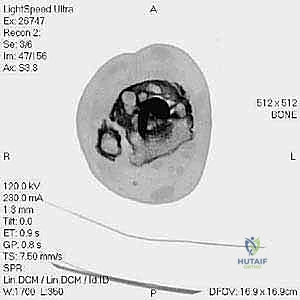

- التصوير المقطعي المحوسب (CT Scan): وهو الأداة الذهبية لتقييم "المخزون العظمي" (Bone Stock). يوضح بدقة حجم الأكياس العظمية ومقدار العظم المفقود الذي سيحتاج لترقيع.

من أعقد التحديات التي تواجه جراحي العظام هي حدوث كسور في الكعب الداخلي (Medial Malleolus) أو الخارجي (Lateral Malleolus) في وجود مفصل صناعي. تحدث هذه الكسور لعدة أسباب:

1. ترقق العظام: حول المفصل الصناعي نتيجة لعدم استخدام الطرف بشكل طبيعي (Stress Shielding).

2. الاصطدام الميكانيكي (Impingement): إذا كان حجم المفصل الصناعي أكبر من اللازم، فقد يضغط على الكعبين من الداخل ويؤدي لكسرهما بمرور الوقت.

3. الإصابات المباشرة: مثل السقوط أو التواء الكاحل.

علاج هذه الكسور يتطلب مهارة فائقة من الدكتور محمد هطيف، حيث يتم استخدام تقنيات الجراحة الميكروسكوبية وتثبيت الكسور باستخدام صفائح معدنية دقيقة ومسامير (Locking Plates) دون المساس بثبات المفصل الصناعي، أو يتم دمج علاج الكسر ضمن عملية مراجعة المفصل الكلية إذا كان المفصل نفسه تالفاً.